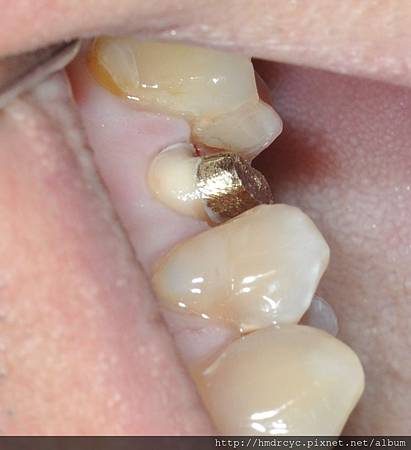

裝上臨時假牙咬合

裝上鑄心後牙齒的高度寬度都恢復

門面重建了K小姐也不再擔心

等牙齒製作全瓷牙冠完成後

可以期待恢復功能與美觀性